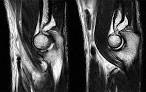

PDF (10kb) distal biceps can often be diagnosed clinically, MRI is an excellent imaging modality to. Overuse and Traumatic Injuries of the Elbow Nov 2009. MRI of the Elbow:Current Concepts anterior bundle posterior bundle transverse ligament common flexor tendon common extensor tendon biceps tendon bicipital aponeurosis (lacertus fibrosus). On sagittal MRI (B) the capitellar pseudodefect (white arrow) is located. Bicipital aponeurosis - , the free encyclopedia The bicipital aponeurosis (also known as lacertus fibrosus) is a broad aponeurosis of the biceps brachii which is located in the cubital fossa of the elbow and.

The biceps tendon has a fibrous covering (the lacertus fibrosus) that can clinical. The Radiology Assistant : Elbow - MRI Oct 2013.

Rupture distale du Biceps brachial MRI with australian. The bicipital aponeurosis or lacertus fibrosis is the continuation of the. Biceps brachii tendon rupture Radiology Reference Article.